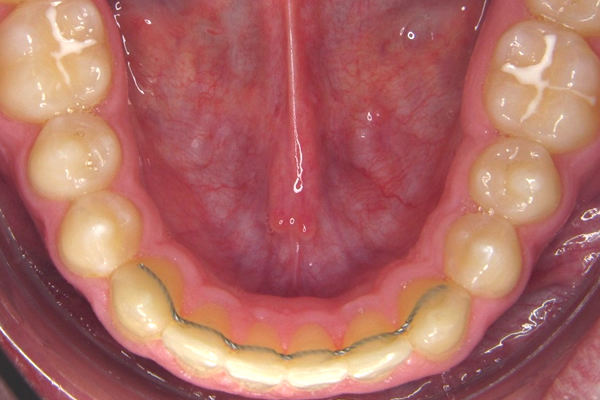

Retainer

Nach Abschluss jeder kieferorthopädischen Behandlung muss die Gebisssituation durch entsprechende Retentionsgeräte gesichert werden.

Die Dauer dieser Stabilisierung ist unterschiedlich, in der Regel 1 bis 2 Jahre.

Empfehlenswert ist die Verwendung eines geklebten Retainers, der unsichtbar an den Innenseiten der Zähne befestigt wird und auch über das Behandlungsende hinaus für eine stabile Gebisssituation sorgt.